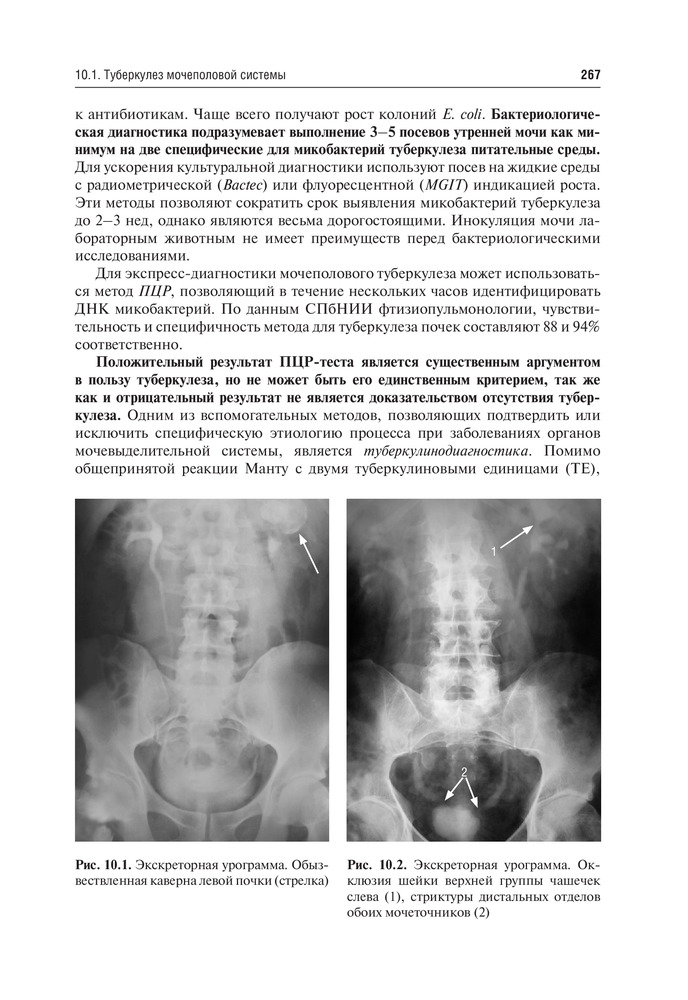

%text%